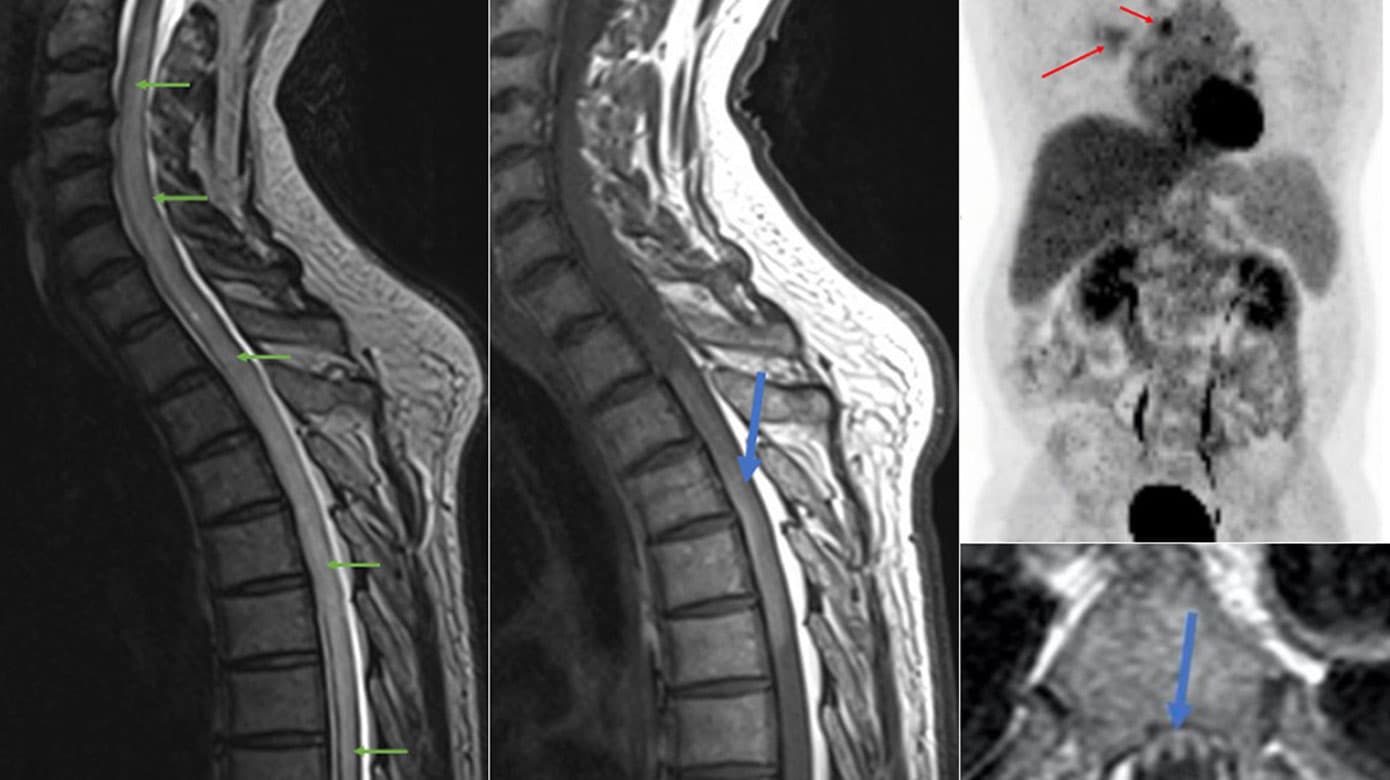

MR-skanning af columna viste kontrastopladende, langstrakt myelitis fra nedre torakale columna op til C2 (Figur 1 A-C). Cerebrospinalvæske (CSV)-undersøgelse viste lymfocytær pleocytose på otte celler og forhøjet proteinniveau på 1,74 g/l, men normalt IgG-indeks. Ekstensive, mikrobiologiske undersøgelser samt autoimmune antistoffer (anti-MOG, anti-aquaporin4, paraneoplastisk pakke og autoimmun encefalitis) var negative. Plasma- og CSV-peptidyldipeptidase A (ACE)- samt serum-interleukin-2-receptor (IL2R)-niveauer var normale. Patienten blev behandlet med methylprednisolon (MP) 1 g intravenøst (i.v.) i fem dage og 50 mg prednisolon efter udskrivelse med eklatant effekt, klinisk og på MR-skanning. Imidlertid indtraf hurtigt recidiv efter prednisolonudtrapning to måneder senere.

PET-CT viste talrige hypermetabole, forstørrede lymfeknuder i mediastinum (Figur 1 D). Biopsi viste nonkaseøs, granulomatøs reaktion ikke uforenelig med sarkoidose. På trods af ny bedring på MP 1 g i.v. i fem dage sås hurtig forværring ved prednisolondosis < 75 mg dagligt. Samtidig udviklede patienten ortostatisk hypotension, der umuliggjorde stående stilling længere end 30 sekunder. Tillæg af MMT og plasmaferese var kun med mindre forbedringer, hvorfor tumornekrosefaktor-α-hæmmerbehandling blev opstartet. Denne behandling førte til næsten fuld remission af symptomer og MR-skanningsforandringer. Efter seks måneder var der imidlertid ny forværring med tiltagende, nedsat kraft i ben. Der opstod mistanke om sarkoid myopati, som blev bekræftet ved muskelbiopsi, samtidig med, at MR-skanning af rygmarven viste recidiv af myelitis, hvorfor behandlingen ændredes til 1.000 mg abatacept hver fjerde uge.